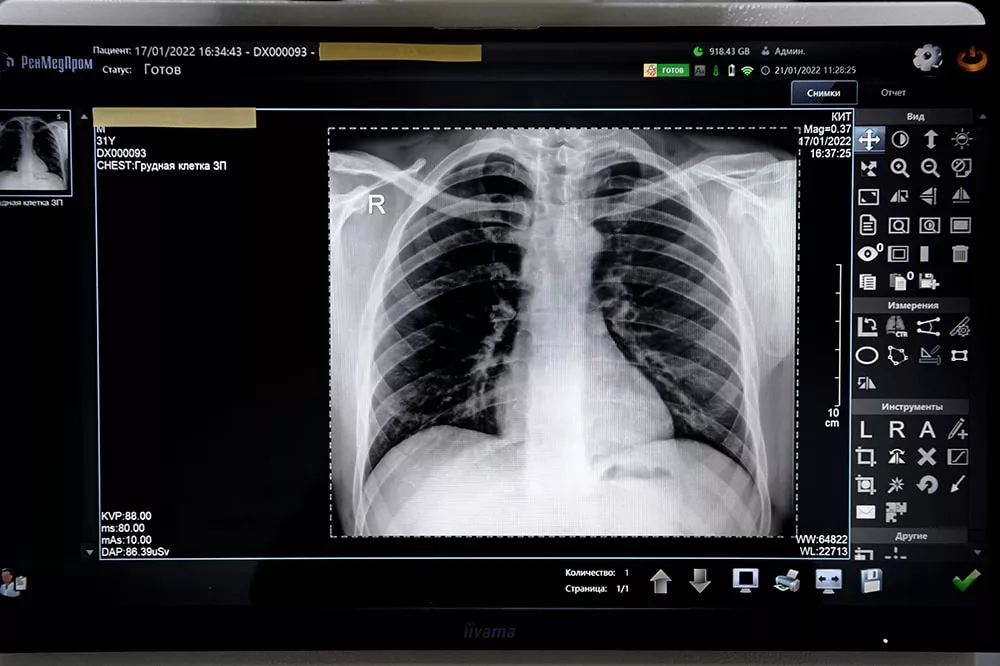

Рентгенография в клинике «КИТ»

Если вам нужна быстрая и качественная рентген-диагностика, обращайтесь в Клинику Ильи Труханова в Куркино. К вашим услугам современное высокоточное оборудование, уютные диагностические кабинеты и опытные специалисты. Наши врачи обладают уникальной базой теоретических и практических знаний в области радиологии. Они проведут быструю и комфортную рентгенографию, интерпретируют результаты исследования и ответят на все ваши вопросы. Точные, детализированные снимки и их грамотная расшифровка позволят врачу поставить верный диагноз и назначить пациенту адекватное лечение.